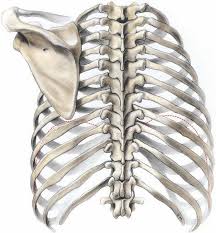

Las costillas se articulan con la columna vertebral en dos puntos diferentes:

- La cabeza de la costilla en la parte lateral de dos cuerpos vertebrales, la articulación de la cabeza de la costilla.

- El tubérculo de la costilla con el vértice del proceso o apófisis transverso, la articulación costotransversa.

La articulación de la cabeza de la costilla tiene superficies articulares que están representadas de la siguiente forma:

- Por parte dela costilla: la cabeza de la costilla con sus caras articulares planas, superior e inferior, oblicuas entre sí y separadas por una cresta anteroposterior; se articulan con las dos vértebras contiguas.

- En las vértebras, hay dos caras similares, las fositas costales, una en cada vértebra, separadas entre sí por el disco intervertebral. Ambas forman un ángulo abierto lateralmente en el que se aloja la cabeza costal (sinoviales planas).

Entre las doce articulaciones costovertebrales, las que corresponden a las extremidades de la serie 1.ª,11.ª y12.ª presentan características propias. Estas costillas se articulan con una sola vértebra y tienen apenas una articulación sinovial plana con un ligamento interóseo rudimentario o ausente.

La articulación costotransversa reúne el tubérculo costal con el vértice del proceso o apófisis transverso correspondiente (vértebra subyacente). Se trata de una articulación sinovial plana que falta en la 11.ª y en la 12.ª costilla.

La superficie costal, la escarilla articular del tubérculo es oval y ligeramente convexa. Del lado dela vértebra se observa una carilla similar configurada en sentido inverso, la fosita costal del proceso transverso. Su orientación varía según la región que seconsidera:las caras articulares se acercan más al borde inferior de la costilla cuanto más baja es su ubicación en el tórax.

- Lascostillassuperiores están situadas al mismo nivel que los procesos correspondientes.

- Las costillas medias e inferiores están algo por encima de los procesos transversos, tanto más cuanto estas son más inferiores.